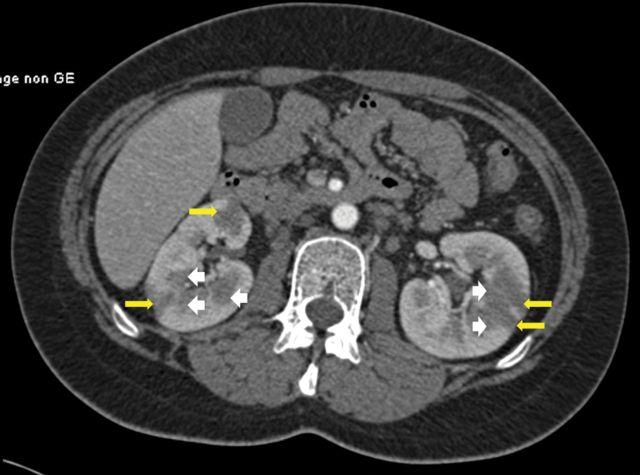

Renal sarcoidosis embraces a wide variety of clinical patterns. Renal vascular involvement has seldom been reported and usually in the setting of systemic vasculitis. We report the case of a 22-year-old patient in whom inaugural manifestation of renal sarcoidosis consisted of severe hypertension associated with bilateral perfusion defects and tumour-like nodules. In the setting of renal sarcoidosis, our case suggests that renin-dependant hypertension may arise from renal ischaemia as a result of extrinsic compression of kidney blood vessels due to severe granulomatous inflammation.

肾结节病有多种临床类型。肾血管受累鲜有报道,且通常发生在系统性血管炎的背景下。我们报告一例22岁患者,其肾结节病的首发表现为严重高血压,伴有双侧灌注缺损和肿瘤样结节。在肾结节病的情况下,我们的病例提示,肾素依赖性高血压可能源于严重肉芽肿性炎症导致肾血管外部受压引起的肾缺血。